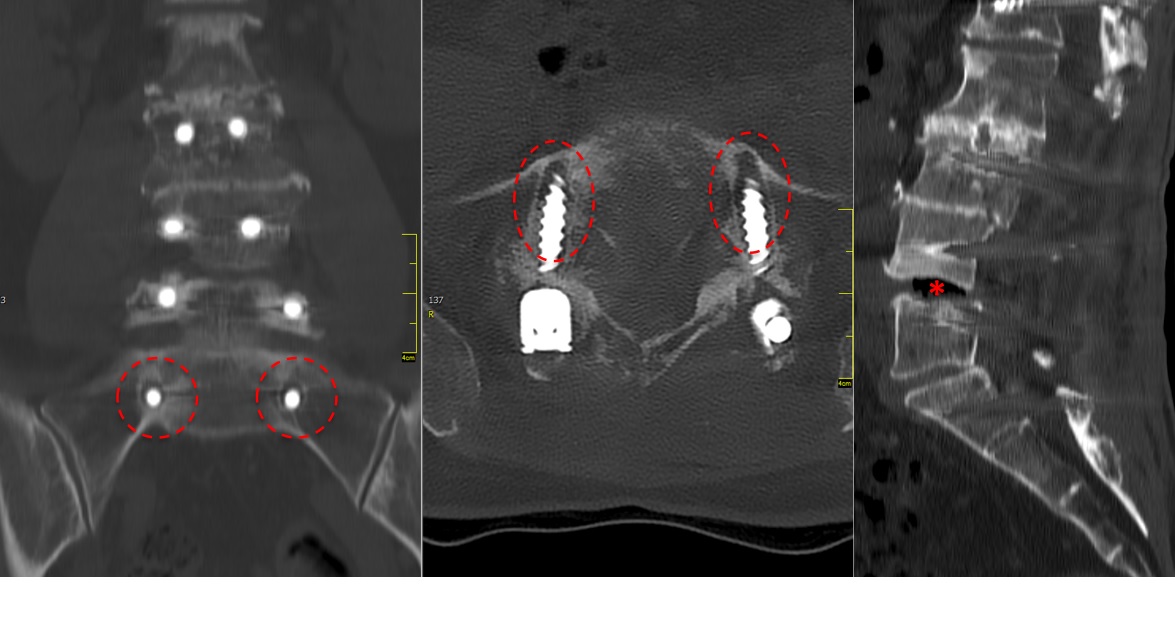

A CT scan allowed a more detailed assessment (Fig 7). There was an obvious nonunion at L5/S1, with loose screws in the sacrum (red circle). Furthermore, there was instability at L4/L5 as the intervertebral disc presented with an important vacuum phenomenon (asterisk). Foraminal stenosis at L5/S1 (not shown) seemed to be the reason behind the persistent leg pain.

The treatment plan was an anterior height restoration and fusion of L5/S1 and L4/L5. A posterior revision surgery was not considered due to the wide decompression and obvious scar formation. For the correction of level L4/L5, an oblique anterolateral approach (OLIF) was selected due to considerable calcification of the aorta and the iliac vessels. At the L5/S1 level, a straight anterior approach was selected and an additional plate fixation (ATB) was performed.